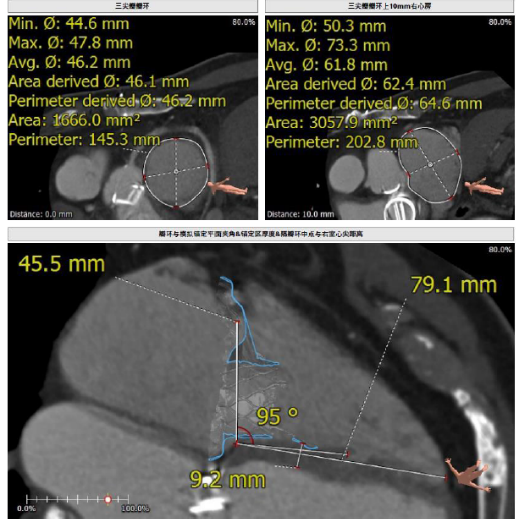

接受本次治療的是一例三尖瓣重度反流的患者,NYHA心功能Ⅲ級。主訴“反復活動后氣促1年,下肢水腫4個月”。入院N末端B型腦鈉肽前體(NT-proBNP)3161pg/ml。心電圖提示:心房顫動,ST-T改變。術前超聲提示:重度三尖瓣關閉不全,右心房擴大,三尖瓣收縮期位移(TAPSE)14mm,左房增大,左室收縮功能正常低值,主動脈瓣、二尖瓣機械瓣功能良好。術前CT評估(圖1):三尖瓣瓣環(周長換算直徑)大小為46.2mm;入路血管無嚴重迂曲,無鈣化;雙側冠脈有鈣化。